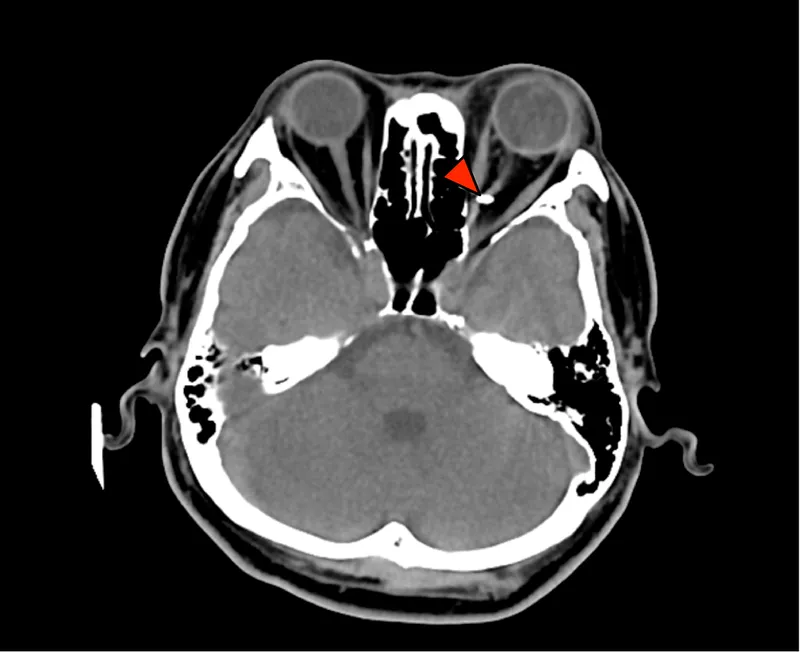

⭐ 'Teardrop sign' on CT scan is characteristic of an orbital floor blowout fracture with herniation of orbital contents into the maxillary sinus.

| Blowout | Floor (maxillary), Medial wall (ethmoid) | Diplopia (esp. up/downgaze), Enophthalmos >2mm, Infraorbital anesthesia, Restricted EOM (inf. rectus) | 'Teardrop', 'Hanging drop' |